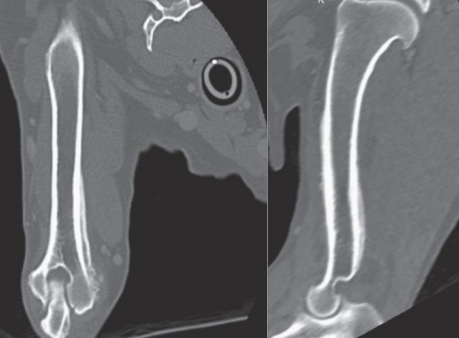

- 일부 경우 원발 병변을 확인하기 위해 CT, MRI가 필요할 수 있다.